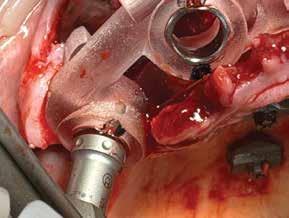

72 FDC 2026 Speaker: Full Arch Implant Reconstruction in the Digital Era: Past, Present and Future